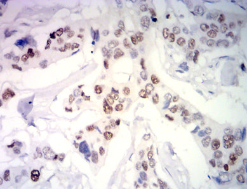

IHC    1/200-1/1000